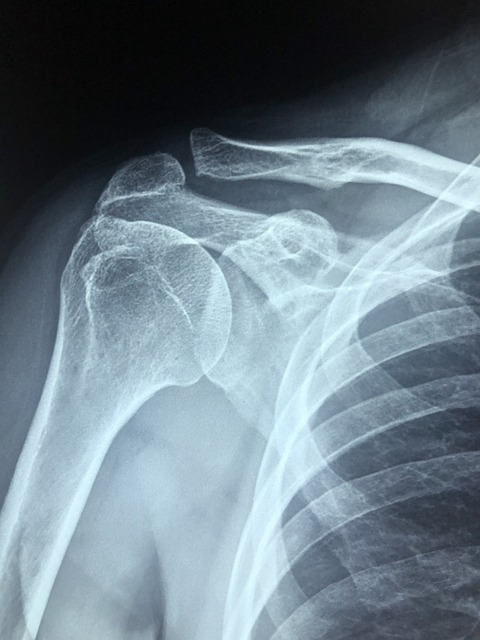

3) 잦은 골절

특히 엉덩이, 손목, 척추의 뼈는 사소한 넘어짐이나 약간의 충격에도 쉽게 부러질 수 있습니다.